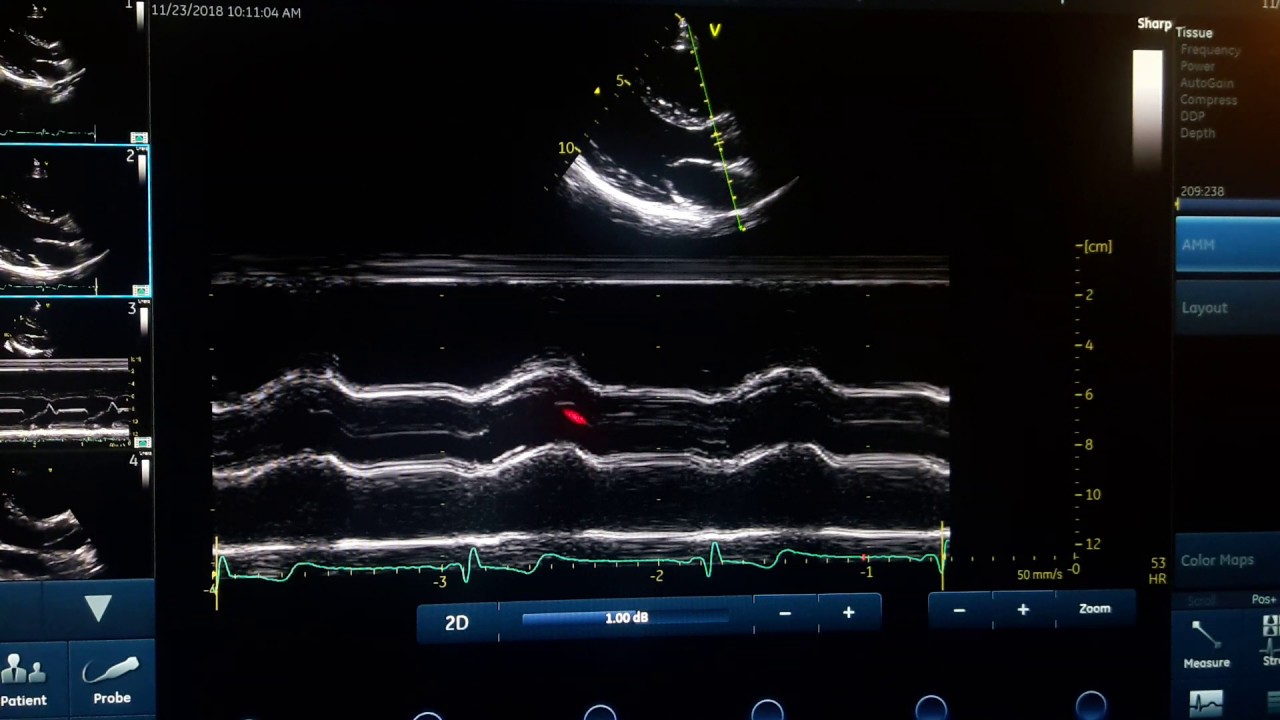

общая концепция m-режима